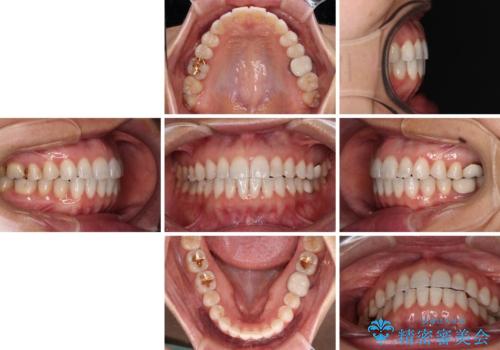

ちょっとしたデコボコをしっかりと改善したい インビザライン矯正

デコボコはあっという間に解消されましたが、上下前歯の隙間がなかなか解消されませんでした。

飲み込みの際に舌を前方に突出する癖があり、飲み込みの度に前歯に強く接触していたため、上下前歯の隙間が維持されていました。

舌の訓練を徹底していただいたことで、徐々に隙間は解消され、きれいな歯列に整えることができました。